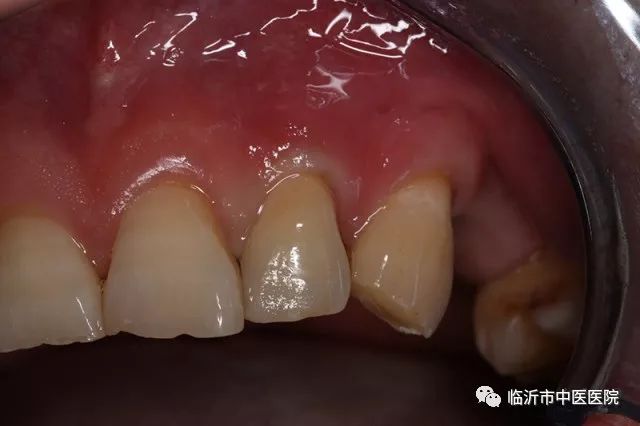

徐宝军主任说,前牙外伤折断,可由于受力方向,部位及力量的大小不同,其折断的部位,形式不一样,修复方法也不一样。当病人就诊时,医生首先要检查患牙折断的部位,牙髓是否暴露。如果门牙折断一小部分,未伤及牙髓,X线显示根端完好,无折断或脱位,牙齿基本稳固,可用粘接方法直接再接断牙。在粘接之前,先清洁牙齿断面,并进行酸蚀处理,用水冲洗,干燥,于断面涂粘接剂,对准位置加压粘接,用光照固化。为加强粘接牢固性,往往在断面采用金属丝支架加固。